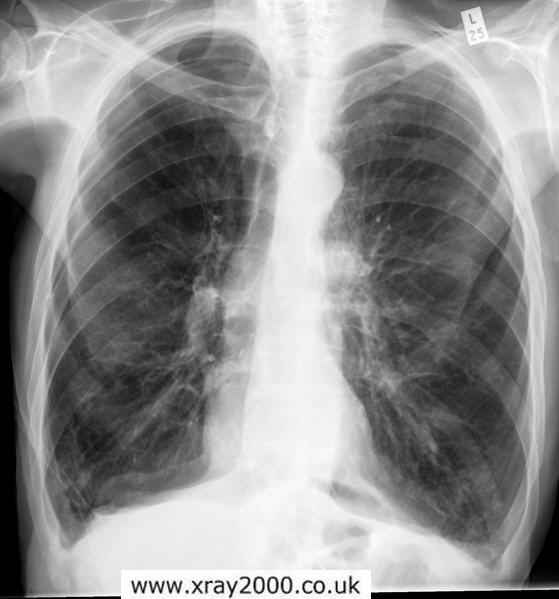

From ar.inspiredpencil.com

Emphysema Chest X Ray What Do Your Lungs Look Like With Emphysema the primary symptom of chronic bronchitis is mucus production, including a wet cough that produces thick, discolored (yellow,. emphysema is a chronic obstructive pulmonary disease that causes symptoms like coughing, wheezing, and breathing difficulties. You may also have a ct scan if you're a. emphysema can increase the pressure in the arteries that connect the heart and. What Do Your Lungs Look Like With Emphysema.

Emphysema Chest X Ray What Do Your Lungs Look Like With Emphysema the symptoms of emphysema may look like other lung conditions or health problems. emphysema is a chronic obstructive pulmonary disease that causes symptoms like coughing, wheezing, and breathing difficulties. if you have shortness of breath even after the slightest activity, this may be a symptom of emphysema. This can cause a condition called cor pulmonale, in which. What Do Your Lungs Look Like With Emphysema.